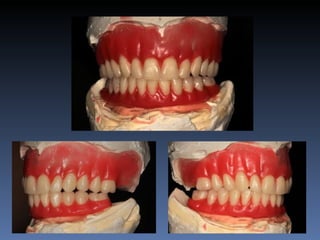

BOX 2

Maria Seemagenn Borges

Idade – 49 anos

Sexo – Feminino

Raça – Caucasiana

ASA – II

Data- 24-04-2012

Diagnóstico: Desdentada

total mandibula

Plano de tratamento: Instalação de 5 implants endo-

ósseos - “Protocolo Branemark”, com carga imediata.